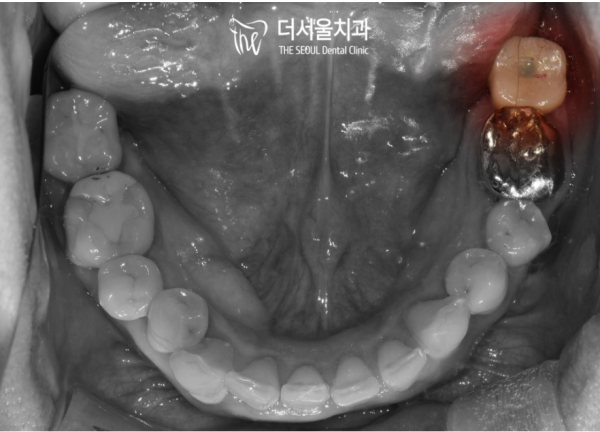

이렇게 육안으로 보시면 사랑니가 살짝 보이는것을 알 수 없습니다.

이렇게 누워있는 사랑니들은 문제를 일으키는 경우가 많기 때문에

사랑니가 나는것 같다는 생각이 들면, 치과에 내원하셔서

사랑니를 발치해야 하는지, 언제쯤 발치하는게 좋은지 등을

진료받으시는게 좋습니다.

If you look at it with your naked eye, you can't see the wisdom teeth slightly.

Wisdom teeth lying down like this often cause problems

If you think you're getting wisdom teeth, visit the dentist

Whether I should remove my wisdom tooth, when is the best time to remove it, etc

You'd better see a doctor.

환자분께 상태를 설명드리고 자연치아를 지킬수 있는 방법을 알려드렸으나

임플란트를 원하셔서 사랑니와 인접치를 발치한 후 임플란트를 심어드리기로 하였습니다.

I explained the patient's condition and told him how to protect his natural teeth

Since you want an implant, we decided to remove the wisdom teeth and adjacent teeth and then implant them.